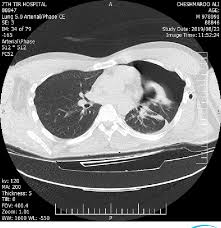

흉부 CT는 폐와 기관지, 심장 주변 구조까지 정밀하게 확인할 수 있는 검사로, 단순 X-ray보다 훨씬 자세한 정보를 제공합니다. 특히 초기 단계의 질환도 발견할 수 있어 진단 정확도가 높은 검사입니다.

증상이 없더라도 건강검진에서 활용되며, 폐 질환이나 종양, 염증 등을 확인하는 데 매우 중요한 역할을 합니다.

흉부 CT는 폐 내부 구조를 상세하게 보여주기 때문에 폐렴, 폐결핵, 폐섬유화 등 다양한 폐 질환을 확인할 수 있습니다.

특히 초기 폐 질환은 X-ray에서 보이지 않는 경우도 있어 CT 검사가 더 정확합니다.

흉부 CT는 폐암을 조기에 발견하는 데 매우 중요한 검사입니다. 작은 결절이나 종양도 확인할 수 있어 조기 진단이 가능합니다.